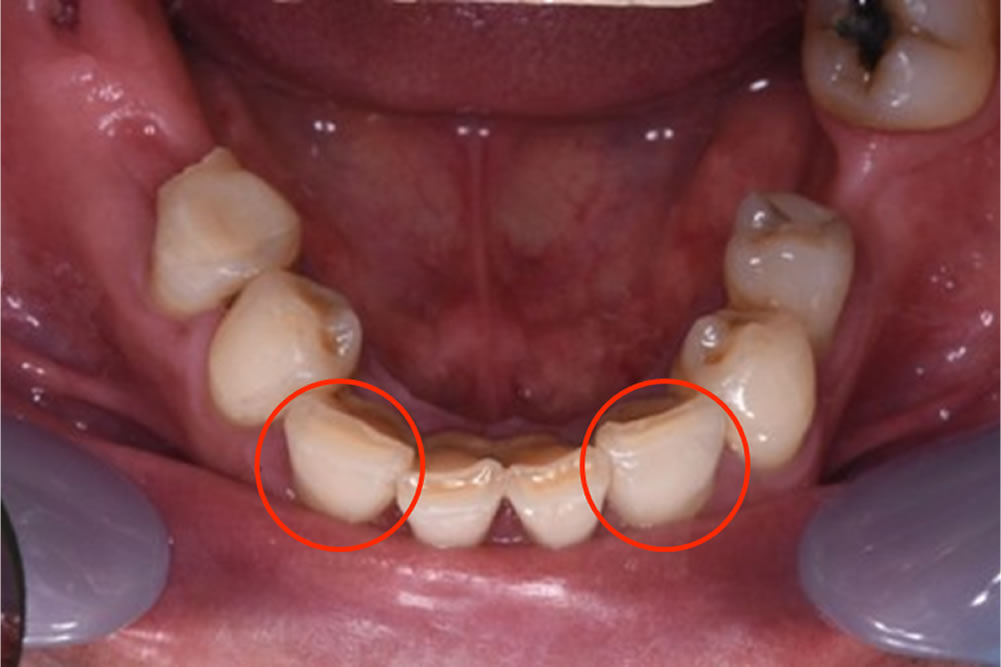

初診時の口腔内

口腔内は全顎崩壊している状態で、すぐにでも抜歯をしたほうがよい状態の歯が多数ありました。痛みも伴っていることから、まずは痛みの改善が最優先事項と考え、必要部位の抜歯を治療計画立案に先立って行いました。

保存困難で抜歯をした部位は写真の赤丸です。

抜歯後の口腔内写真

抜歯後の口腔内写真です。歯茎は赤く腫れ上がり、歯石も帯状に付着しています。歯周病治療が必要な状態です。